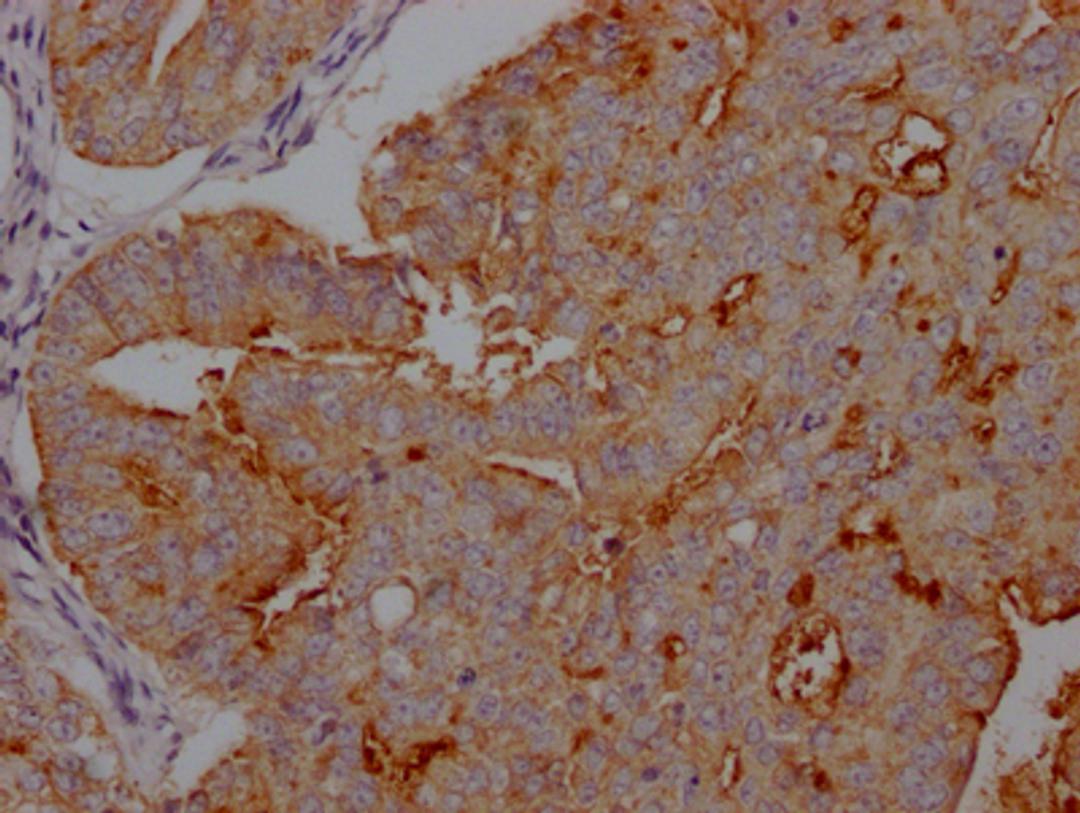

IHC image of CSB-RA941216A0HU diluted at 1:100 and staining in paraffin-embedded human endometrial cancer performed on a Leica BondTM system. After dewaxing and hydration, antigen retrieval was mediated by high pressure in a citrate buffer (pH 6.0). Section was blocked with 10% normal goat serum 30min at RT. Then primary antibody (1% BSA) was incubated at 4℃ overnight. The primary is detected by a Goat anti-rabbit IgG polymer labeled by HRP and visualized using 0.05% DAB.